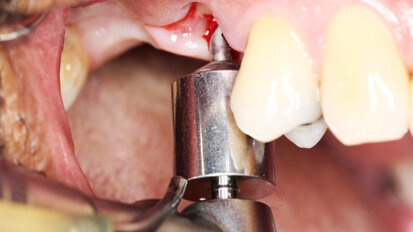

Management kosti a měkkých tkání při komplexní rekonstrukci jednoho zubu implantátem

Rekonstrukce jednoho frontálního zubu implantátem bývá pravděpodobně největší estetickou výzvou pro praktického zubního lékaře. Správné ...